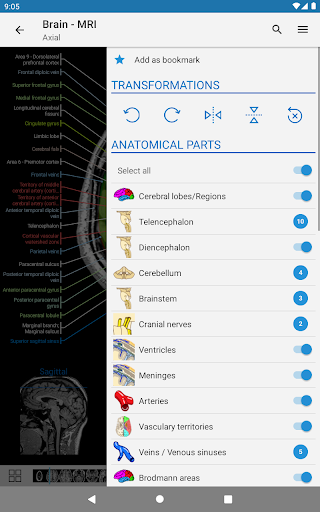

* تجربة مستخدم محسنة مع تحديث ألوان التطبيق

* تحسين التنقل في قائمة الوحدات النمطية مع وضع أفقي محسن على الهاتف المحمول

* تقديم الجداول في تعريفات الهياكل التشريحية لتحسين هيكلة البيانات

* تحسين تسليط الضوء على الروابط الخارجية في التعريفات لتجربة تنقل أكثر سهولة